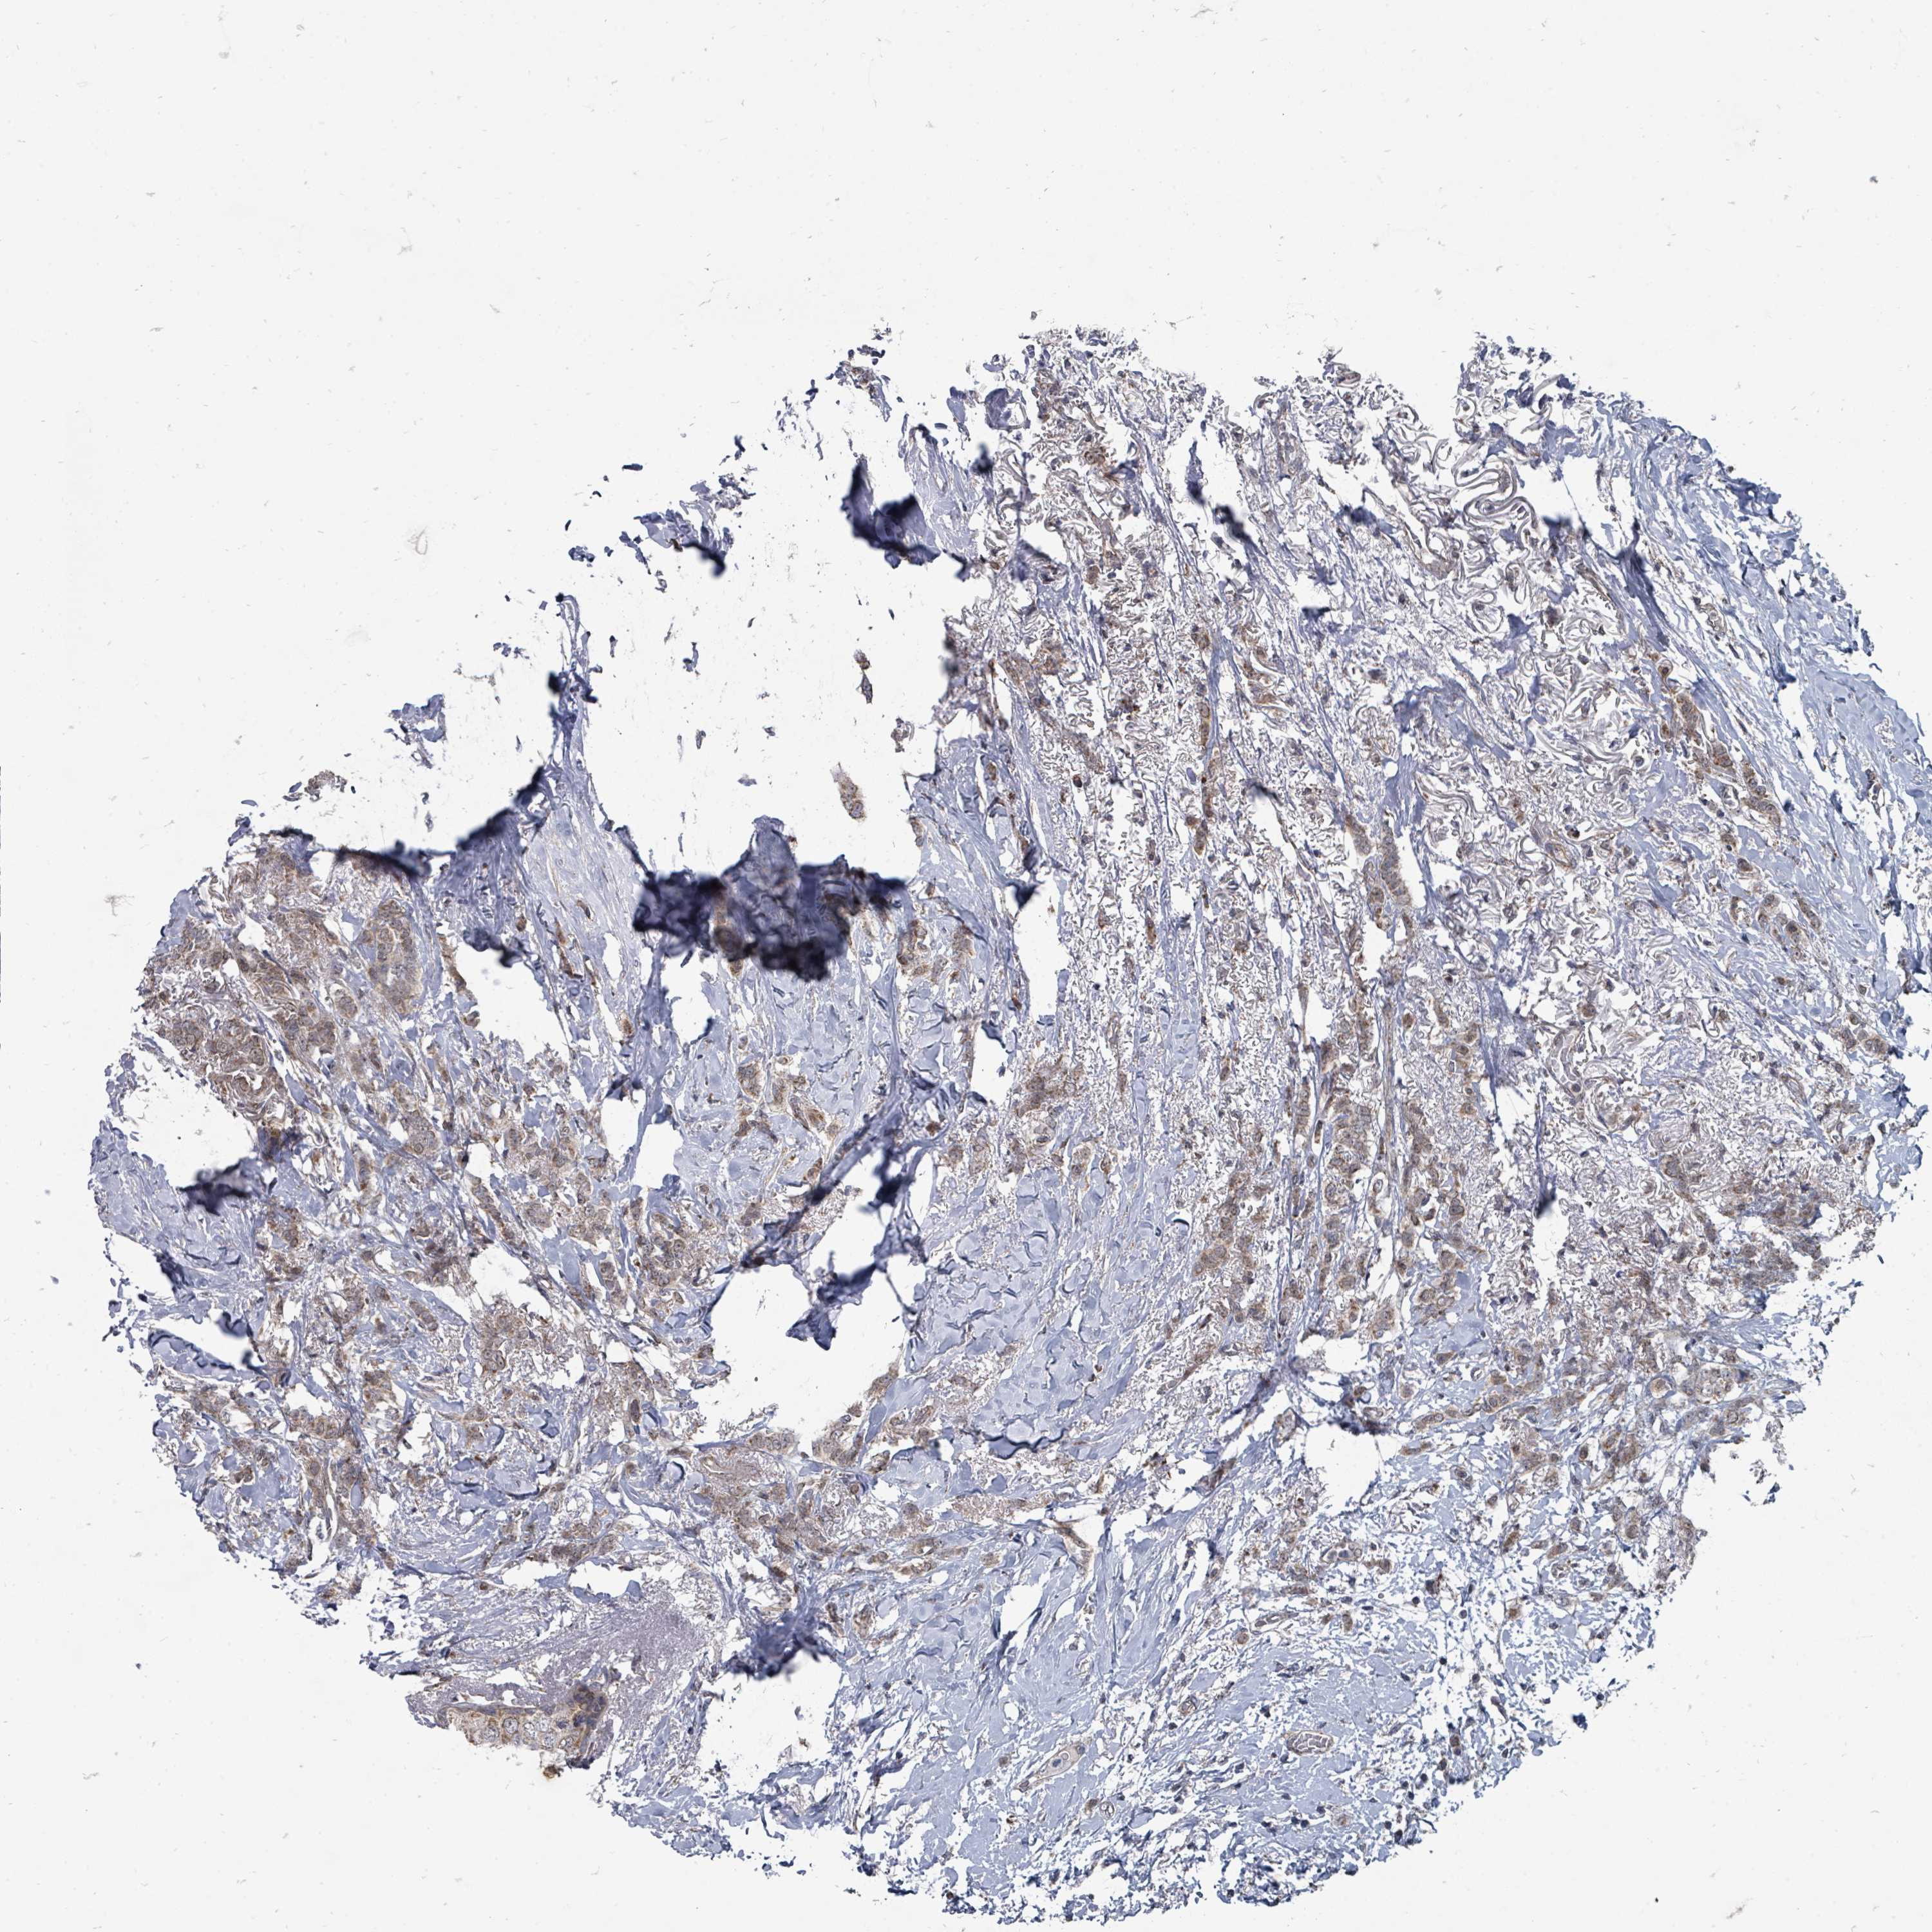

CANCER BREAST CANCER Show tissue menu

BRCA TCGA BRCA VALIDATION PROTEIN EXPRESSION